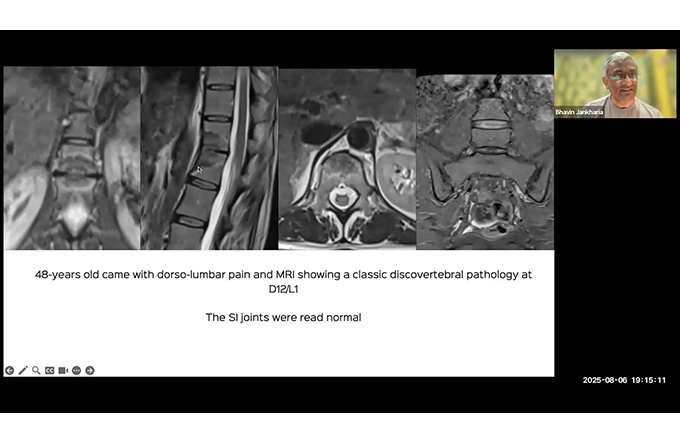

Case based Neuro and Head & Neck Discussion